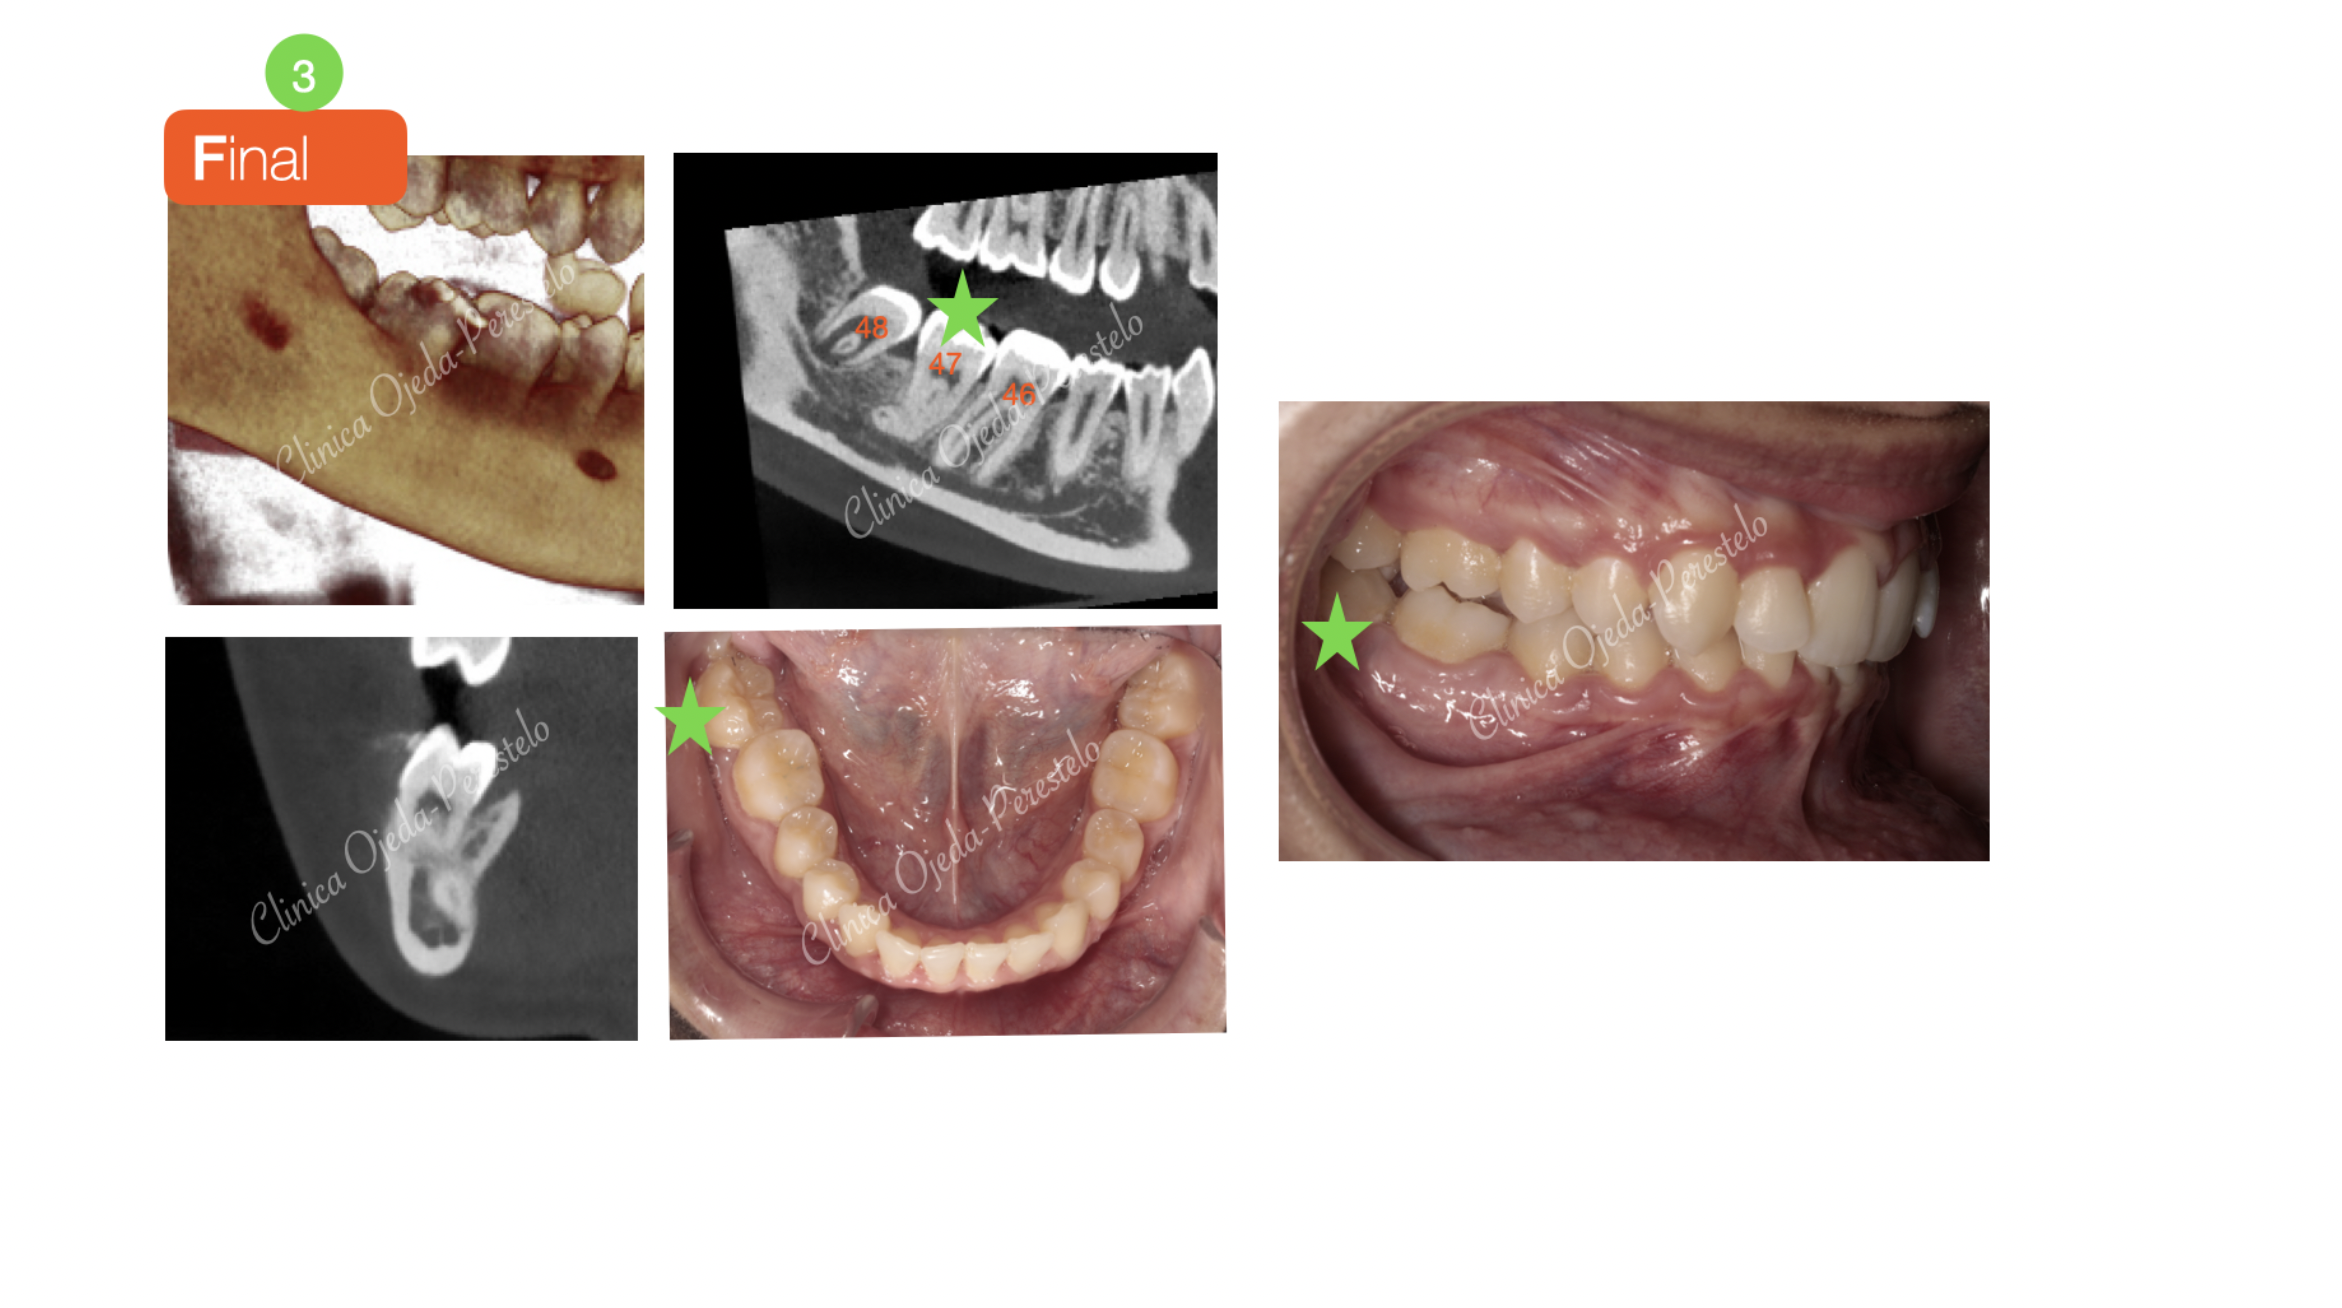

Podemos observar cómo hemos podido reconducir la pieza 47 al plano de oclusión de manera exitosa en un plazo de 15 meses tras la colocación de una Miniplaca semiactiva con tracción ortodoncia continuada. Actualmente la paciente está en fase de comenzar su tratamiento de Ortodoncia Plástica a efectos de poder mejorar la alineación, nivelación y la articulación de sus piezas dentarias.